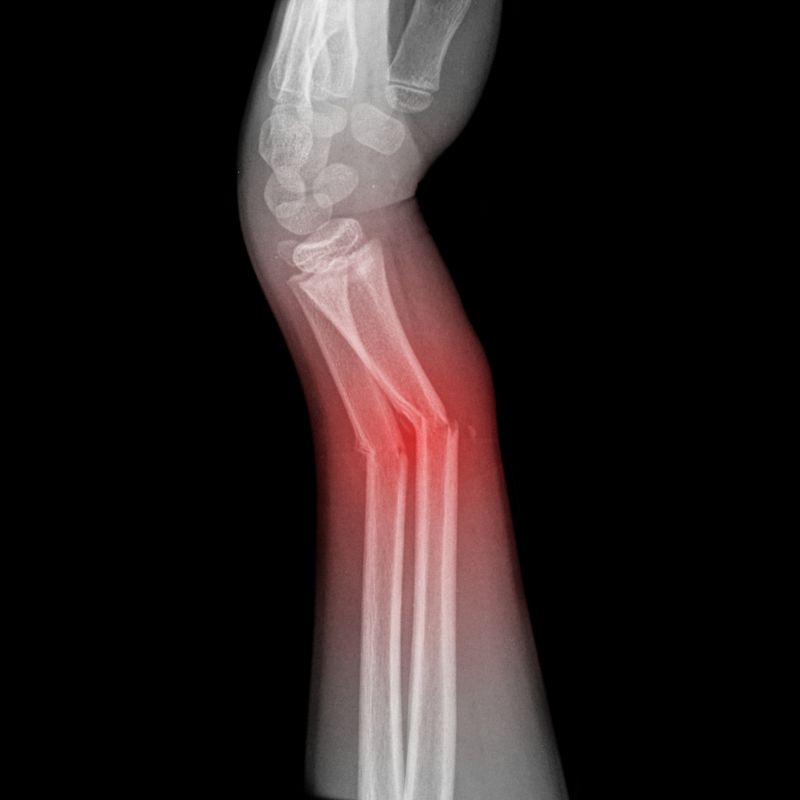

A non-union bone fracture occurs when a bone fails to heal completely after an injury, often leaving a gap or persistent instability. Conversely, a malunion happens when the bone heals in an abnormal position, such as being rotated or shortened. Both conditions require an orthopedic surgeon Austin patients trust to restore proper alignment and function.

Signs of a non-union or malunion include persistent pain at the original break site long after the expected healing period. You might notice swelling, tenderness, or a visible deformity in the limb. If you experience a “clicking” sensation or instability when bearing weight, it is vital to see an orthopedic surgeon immediately for an evaluation.

Treatment often involves reconstruction for non-union fractures using specialized techniques like bone grafting or internal fixation with plates and screws. We focus on stabilizing the site and stimulating biological growth. For malunions, we may perform a corrective osteotomy to realign the bone, ensuring a professional and knowledgeable approach to your surgical care.